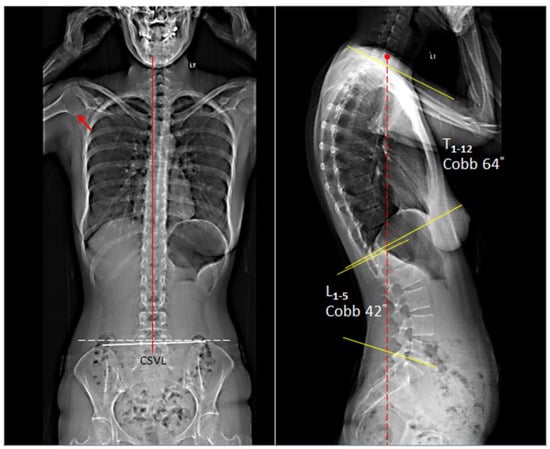

Upon initial evaluation, the patient presented with a forward head and slouching posture. Joint mobility was assessed and indicated restriction at C5–7 and T10-L2 levels. Muscular hypertonicity was evaluated and indicated present in bilateral upper trapezius, levator scapulae, sternocleidomastoid, and subscapularis. Her cervical range of motion was limited and painful at 10° extension (normal > 60°) and 45° of right rotation (normal > 80°). The orthopedic and neurological examinations were within normal limits. Full spine EOS® radiographs showed a picture of degenerative spondylosis of the lower cervical spine with osteophytes at posterior C5 and C6, C7/T1 disc-space narrowing, straightened cervical lordosis, thoracic hyperkyphosis, induced lumbar kyphosis, and cystic change of the right humeral head (Figure 1). Patients presented with a global thoracic curve of 64° and lumbar curve of 42°. In general, the average angle of thoracic kyphosis and lumbar lordosis is 43.55 ± 6.44 and 32.42 ± 6.29, respectively. Based on the symptoms of heartburn relating with neck pain and the exclusion of systemic disorders, the patient was given a diagnosis of upper cross syndrome with GERD.

Figure 1.

EOS® radiographs demonstrating degenerative spondylosis of the lower cervical spine with osteophytes at posterior C5 and C6, C7/T1 disc-space narrowing, straightened cervical lordosis and thoracic hyperkyphosis, and cystic change of the right humeral head (red arrow). In general, the average angle of thoracic kyphosis and lumbar lordosis is 43.55° ± 6.44 and 32.42° ± 6.29, respectively. CSVL: central sacral vertical line (red line).